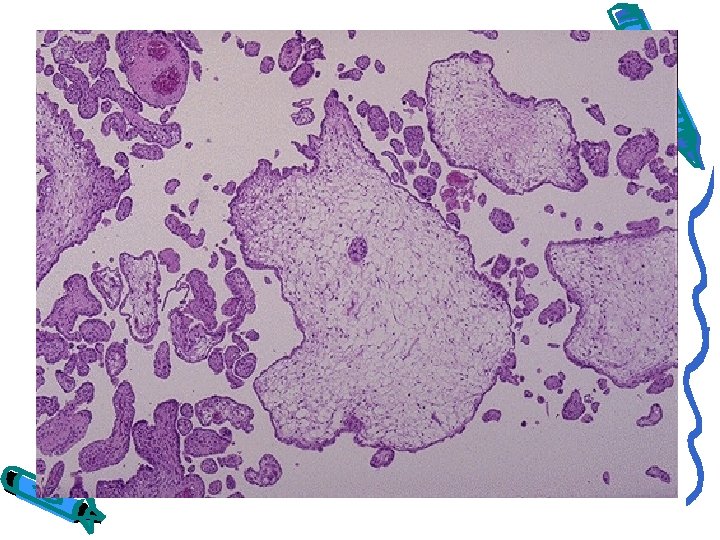

GESTATIONAL TROPHOBLASTIC DISEASE: HYDATIDIFORM MOLE, COMPLETE TYPE Swollen, avascular villi covered by chorionic epithelium (trophoblast) of varying atypia Gross appearance is that of a voluminous mass of grape like structures